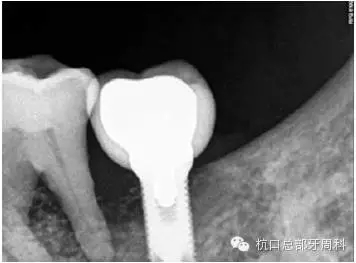

2012.4

113.webp.jpg

2013.1

114.webp.jpg

2013.3

下頜所有牙齒自動(dòng)脫落,炎癥累及整個(gè)下頜骨,包括左側(cè)髁狀突,病理性骨折左側(cè)聽(tīng)力喪失

115.webp.jpg